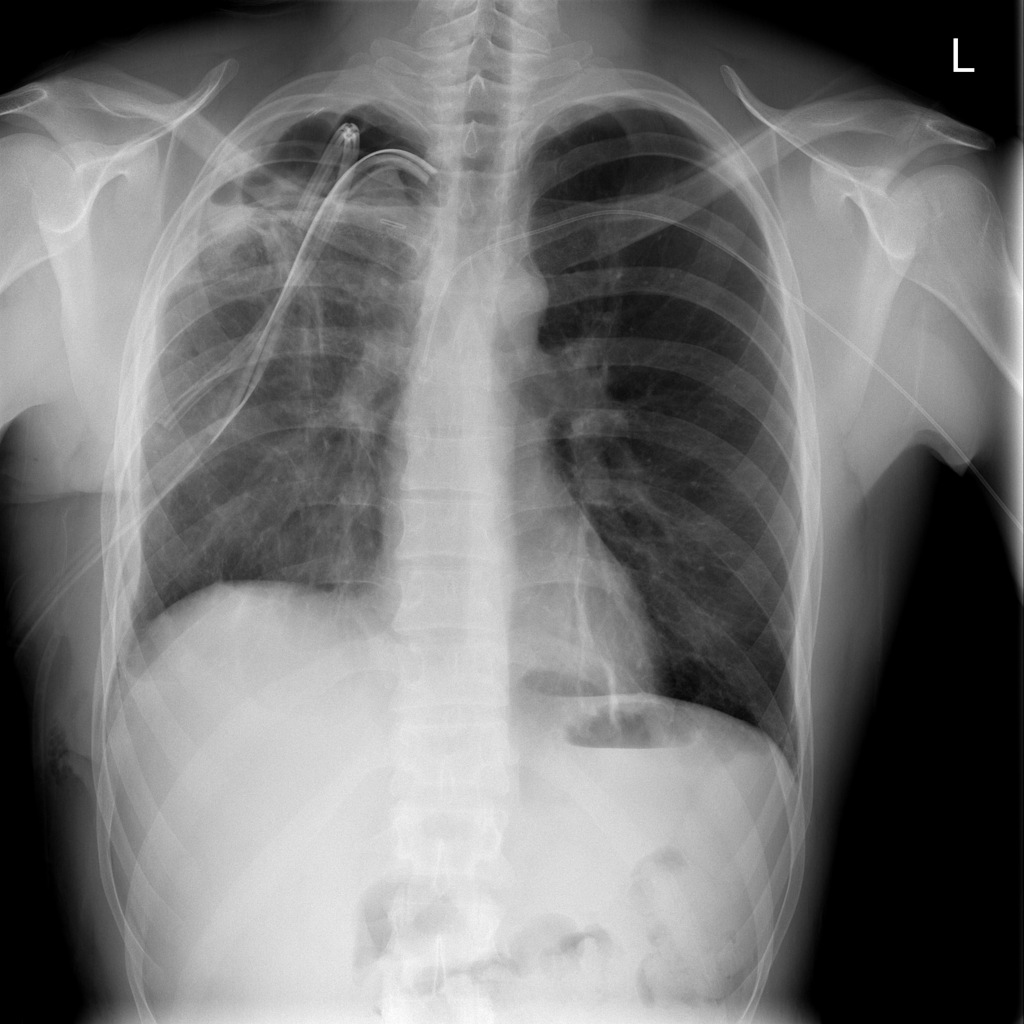

PAT-4639 · IMG-020Pneumothorax

PAT-4639 · IMG-020

PA